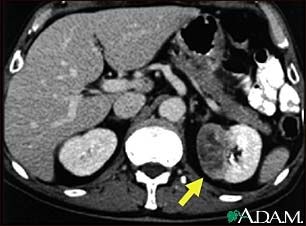

Kidney tumor - CT scan

This CT scan of the abdomen shows a tumor in the left kidney (called hypernephroma, or renal cell carcinoma). It is located on the lower right side of the picture.